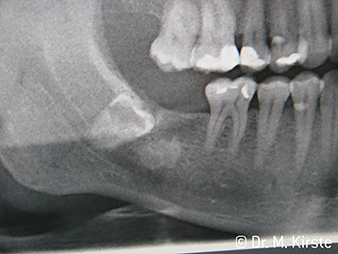

W&H Patient example

Fig. 7:

... is neatly removed using the new contra-angle handpiece.